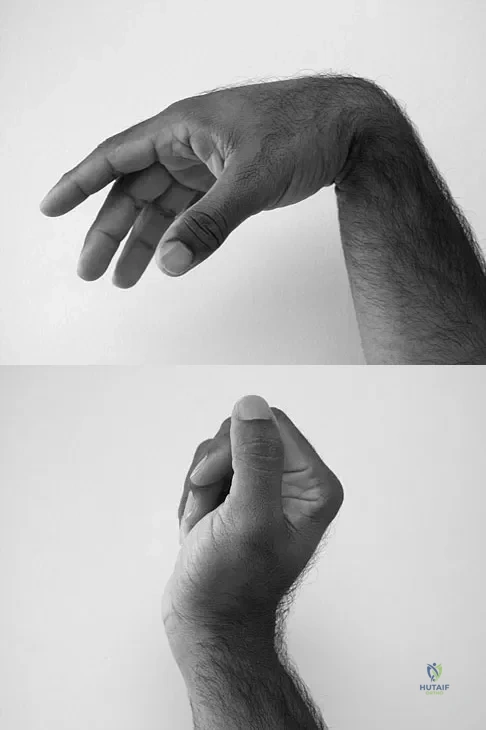

Question 47

A 35-year-old man sustained a 1-inch stab incision in his proximal forearm while trying to use a screwdriver 2 weeks ago. The laceration was routinely closed, and no problems about the incision site were noted. He now reports that he has been unable to straighten his fingers or thumb completely since the injury. Clinical photographs shown in Figures 30a and 30b show the man passively flexing the wrist. What is the most appropriate management?